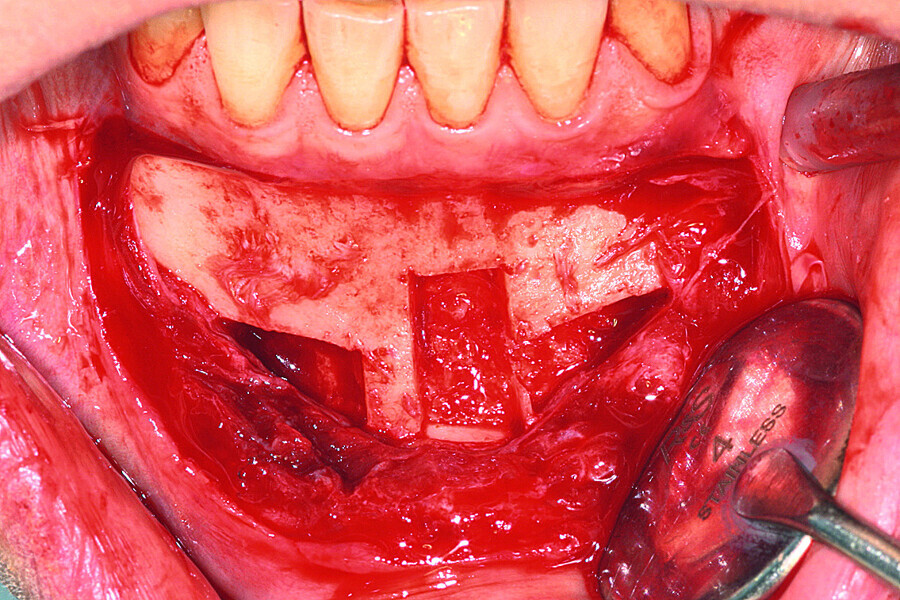

Fig. 6: The grafts were harvested from the chin symphysis and firmly attached by surgical screws in the recipient site.

Fig. 7: The grafts were harvested from the chin symphysis and firmly attached by surgical screws in the recipient site.